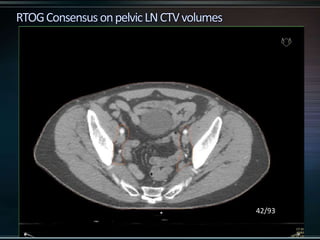

RTOG GU Consensus on pelvic LN CTV volumes:

 Commence contouring the pelvic CTV LN volumes at the L5/ S1

interspace (the level of the distal common iliac and proximal

presacral lymph nodes).

 Place a 7-mm margin around the iliac vessels connecting the

external and internal iliac contours on each slice, carving out

bowel, bladder, and bone.

 Contour presacral lymph nodes from S1 through S3, posterior

border being the anterior sacrum, and anterior border

approximately 10 mm anterior to the anterior sacral bone

carving out bowel, bladder, and bone.

 Stop external iliac CTV lymph node contours at the top of the

femoral heads (bony landmark for the inguinal ligament).

 Stop contours of the obturator CTV lymph nodes at the top of

the symphysis pubis.

RTOG GU Consensuson pelvic LN CTV volumes:  Commence contouring the pelvic CTV LN volumes at the L5/ S1 interspace (the level of the distal common iliac and proximal presacral lymph nodes).  Place a 7-mm margin around the iliac vessels connecting the external and internal iliac contours on each slice, carving out bowel, bladder, and bone.  Contour presacral lymph nodes from S1 through S3, posterior border being the anterior sacrum, and anterior border approximately 10 mm anterior to the anterior sacral bone carving out bowel, bladder, and bone.  Stop external iliac CTV lymph node contours at the top of the femoral heads (bony landmark for the inguinal ligament).  Stop contours of the obturator CTV lymph nodes at the top of the symphysis pubis.